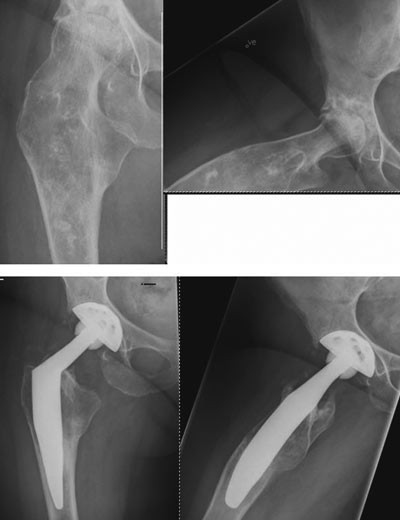

Harris’ hofteskår ble målt preoperativt og postoperativt etter ett år. Gjennomsnittlig skår preoperativt var 49 (spredning 27 – 66) og postoperativt 97 (spredning 76 – 100). Preoperativt var det aktuelle bein kortere (1 – 3 cm) hos 20 pasienter. Postoperativt var beina like lange hos 35 pasienter, hos én pasient var beinet fortsatt 1 cm for kort, og hos én pasient var beinet blitt 1 cm for langt (overkorreksjon). Eksempler på bruk av den individtilpassede hofteprotesen fremgår av figur 6, figur 7 og e-figur 8.